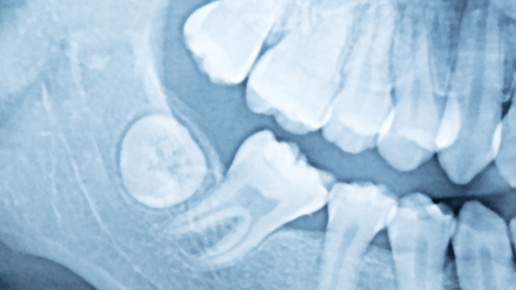

Обратиться к стоматологу, иначе есть риск, что воспаление распространится на соседние ткани лица и шеи. В зависимости от ситуации, врач либо иссечет капюшон, либо удалит проблемный зуб. Чаще всего слизистая воспаляется, когда зуб мудрости прорезывается неправильно. На поверхность показывается только часть зуба, а часть остается прикрытой лоскутом тканей, или «капюшоном». Под капюшон начинают забиваться частички пищи и микробы, которые практически невозможно вычистить зубной щеткой. Это приводит к развитию воспаления — перикоронариту...

Сегодня я расскажу вам про одну очень распространенную проблему, которая гонит даже самых упертых пациентов к стоматологу- перикоронит, он же перикоронарит или, как вы любите, воспаленный капюшон. Википедия нам говорит, что это Перикоронит (перикоронарит) — это воспаление мягких тканей десны, окружающих прорезающийся или прорезавшийся зуб. То есть, теоретически это может возникнуть возле любого зуба, но в 99% это происходит именно с нижними третьими молярами (или, как вы любите, зубами мудрости) По строению зубных рядов тут...